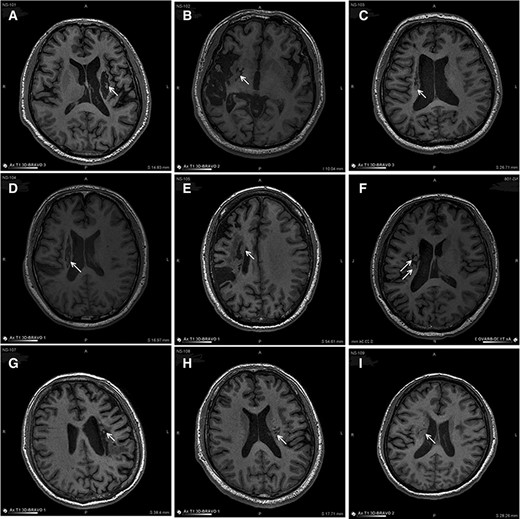

圖中顯示的是所有9名受試者(#101–109)在NSI-566移植后最新隨訪時(shí)的T1MRI圖像。箭頭指示梗塞腔位置。

(A):#101,24個(gè)月時(shí),(B)#102,12個(gè)月時(shí),(C)#103,14個(gè)月時(shí),(D) #104,9個(gè)月時(shí),(E)#105,14個(gè)月時(shí),(F)#106,24個(gè)月時(shí),(G) #107,21個(gè)月時(shí),(H) #108,12個(gè)月時(shí),(I) #109,14個(gè)月時(shí)。所有九個(gè)病例中梗塞腔內(nèi)均有新組織生長。